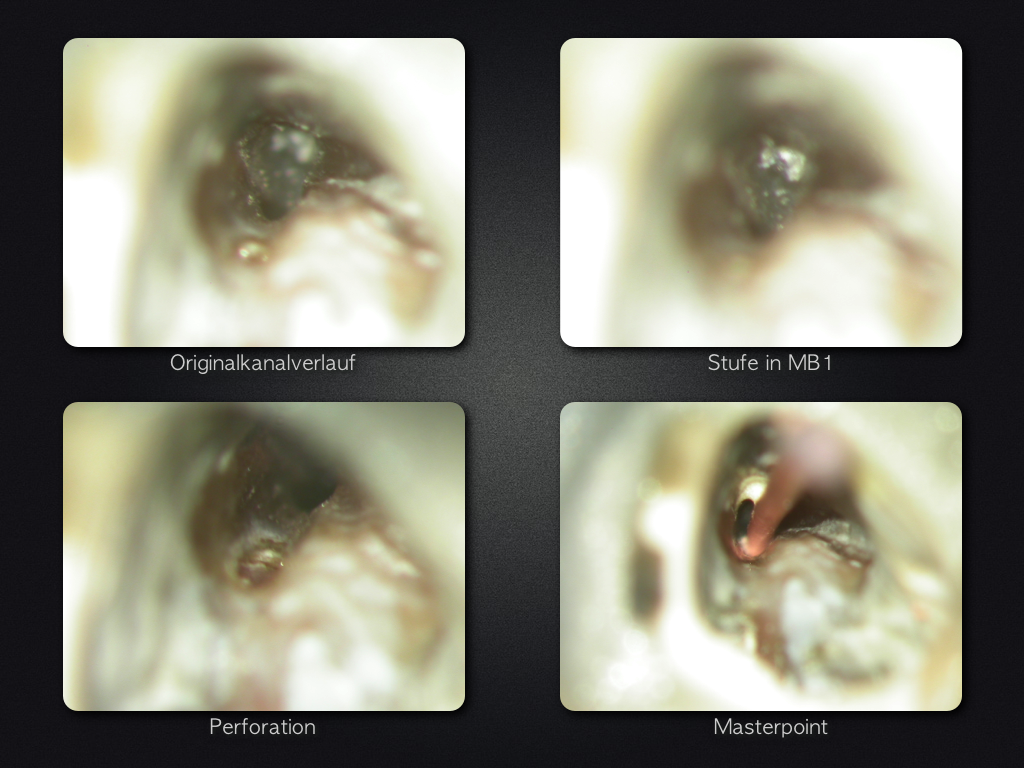

26D.004

Fette Stufe